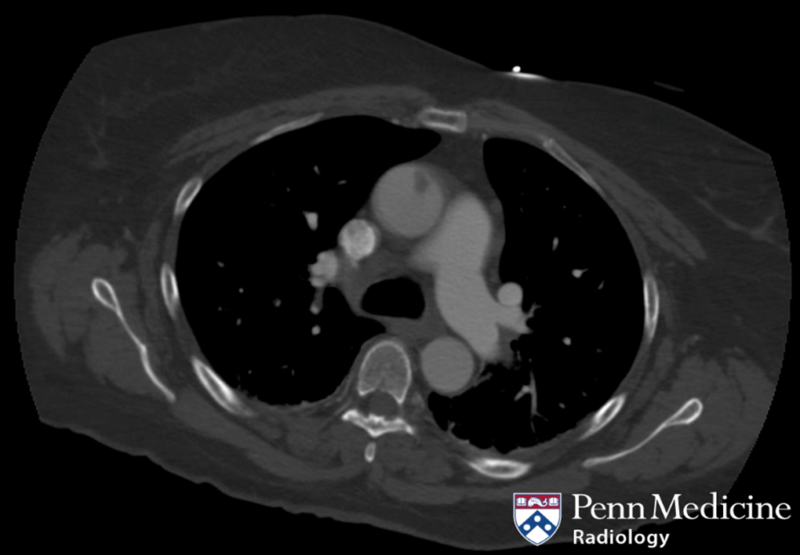

75-year-old woman undergoing thoracic aorta assessment

A 75-year-old woman with a history of hypertension underwent CT angiography of the chest for assessment of the thoracic aorta.

Published Date: February 3, 2026

Tags:

Angiography

,

CT

MRI

Thoracic